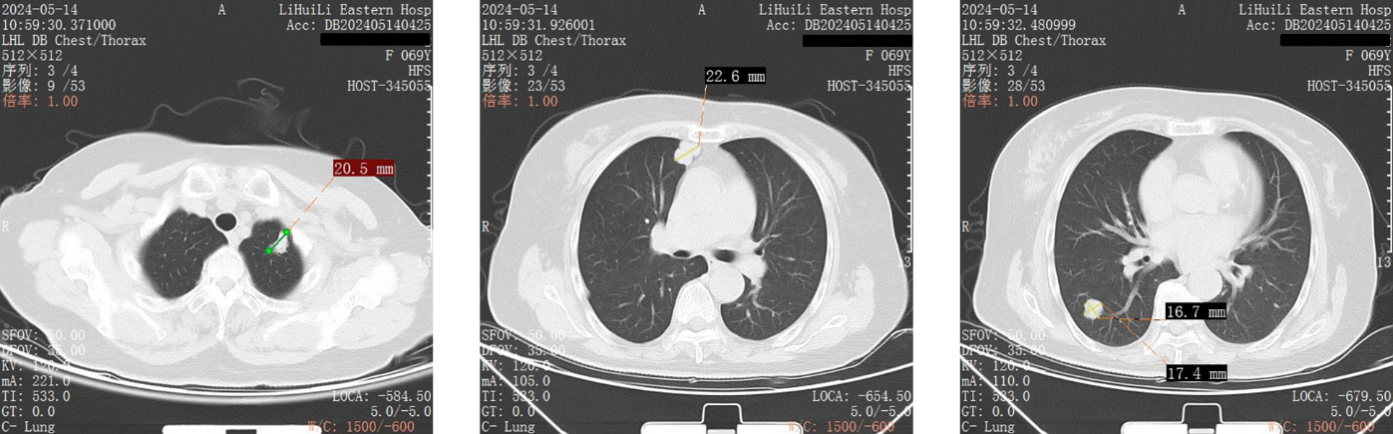

胸部 CT(2024 年 5 月 14 日):右乳占位,右腋下淋巴结肿大;双肺多发转移瘤(较大者 20×15mm),右肺上叶纤维灶。

图1 2024年5月14日胸部CT

疗效评价:治疗 6 周期后,胸部 CT 示双肺转移瘤较基线明显缩小(较大者从 20×15mm 缩小至 10mm 以下),右乳肿块缩小至 1cm 以下,右腋下淋巴结消失,疗效评价为部分缓解(PR)。

图3胸部CT(右左至右:2024年5月14日、2024年7月28日、2024年10月25日、2025年2月28日)